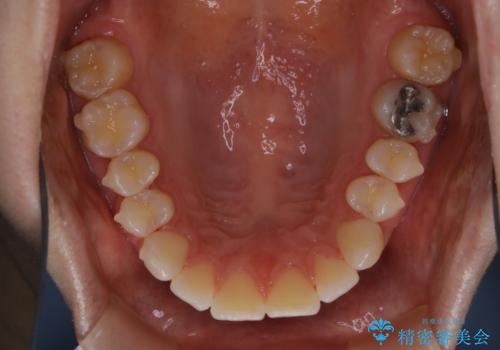

- インビザライン矯正治療中にステインが気になるとのことで来院されました。全体的にステインが付着していたため自費クリーニングPMTC(60分コース)を行いました。

インビザライン矯正治療中は、ご自身の歯にアタッチメントという突起物(効率的に歯の移動を行うため)をつけます。そのため、通常時よりもステインが付きやすい状態になることがあります。

矯正治療中の虫歯・歯周病・口臭予防としても、定期的にPMTCを行うことが大切です。